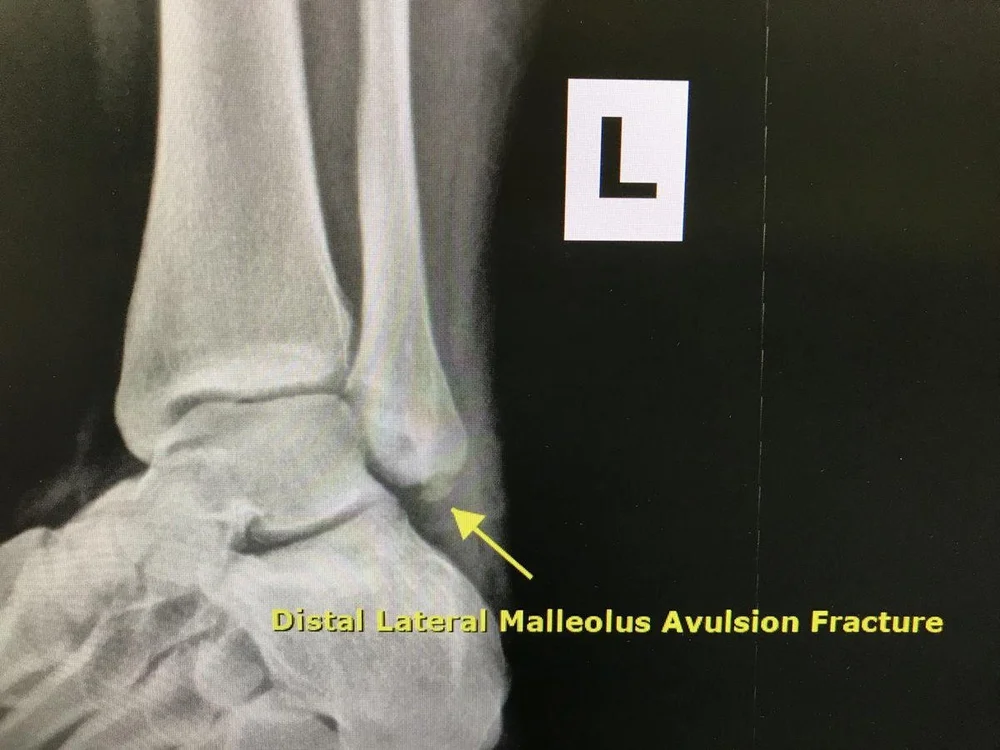

Avulsion Fracture Sports Medicine Information Can You Exercise With An Avulsion Fracture    quick movements, sudden direction changes, or high energy impacts while playing sports can lead to avulsion.   once the fracture has healed, physical therapy can help you regain motion in your ankle.   preventing avulsion fractures involves strengthening muscles and tendons through regular exercise and stretching. If a fracture is more serious,.   the participants also did exercises to. Can You Exercise With An Avulsion Fracture.